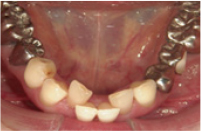

治療前